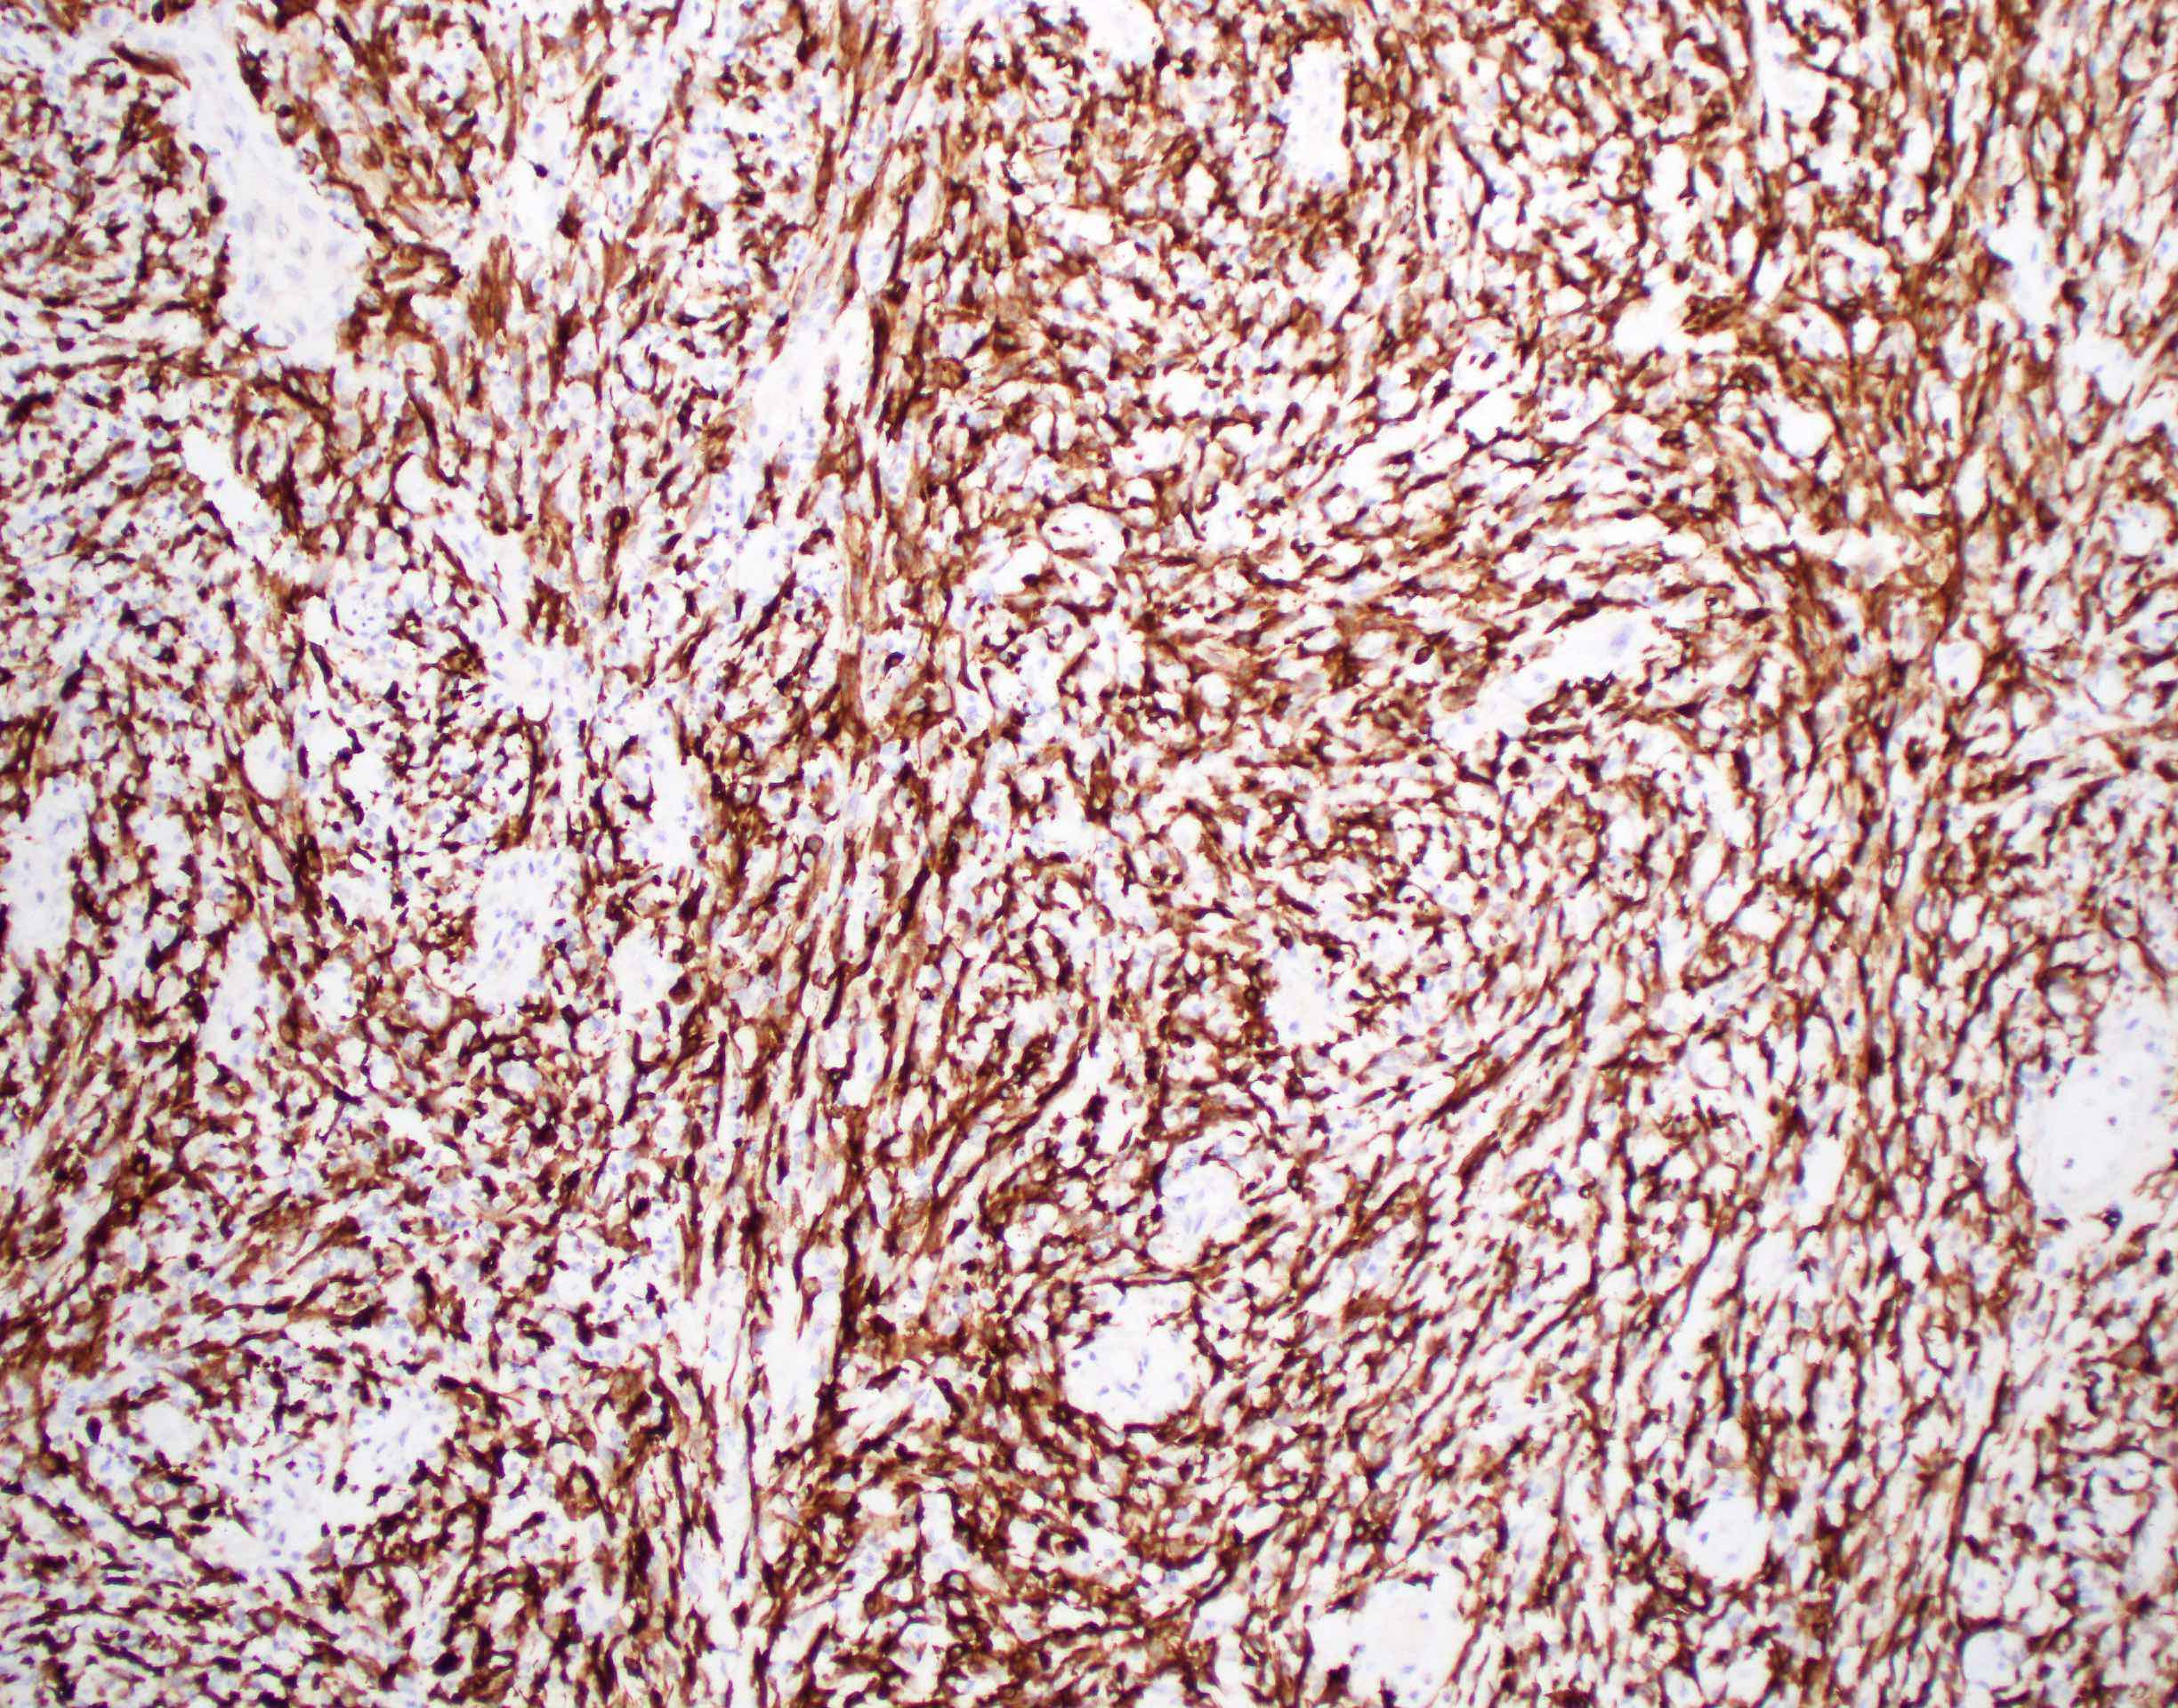

- Spindle cell / sarcomatoid squamous cell carcinoma (Am J Otolaryngol 2008;29:123)

- Most commonly occurs postradiotherapy or as second primary

- Mesenchymal in appearance

- Atypical plump spindled cells arranged in fascicles or storiform pattern

- May have metaplastic or neoplastic cartilage or bone